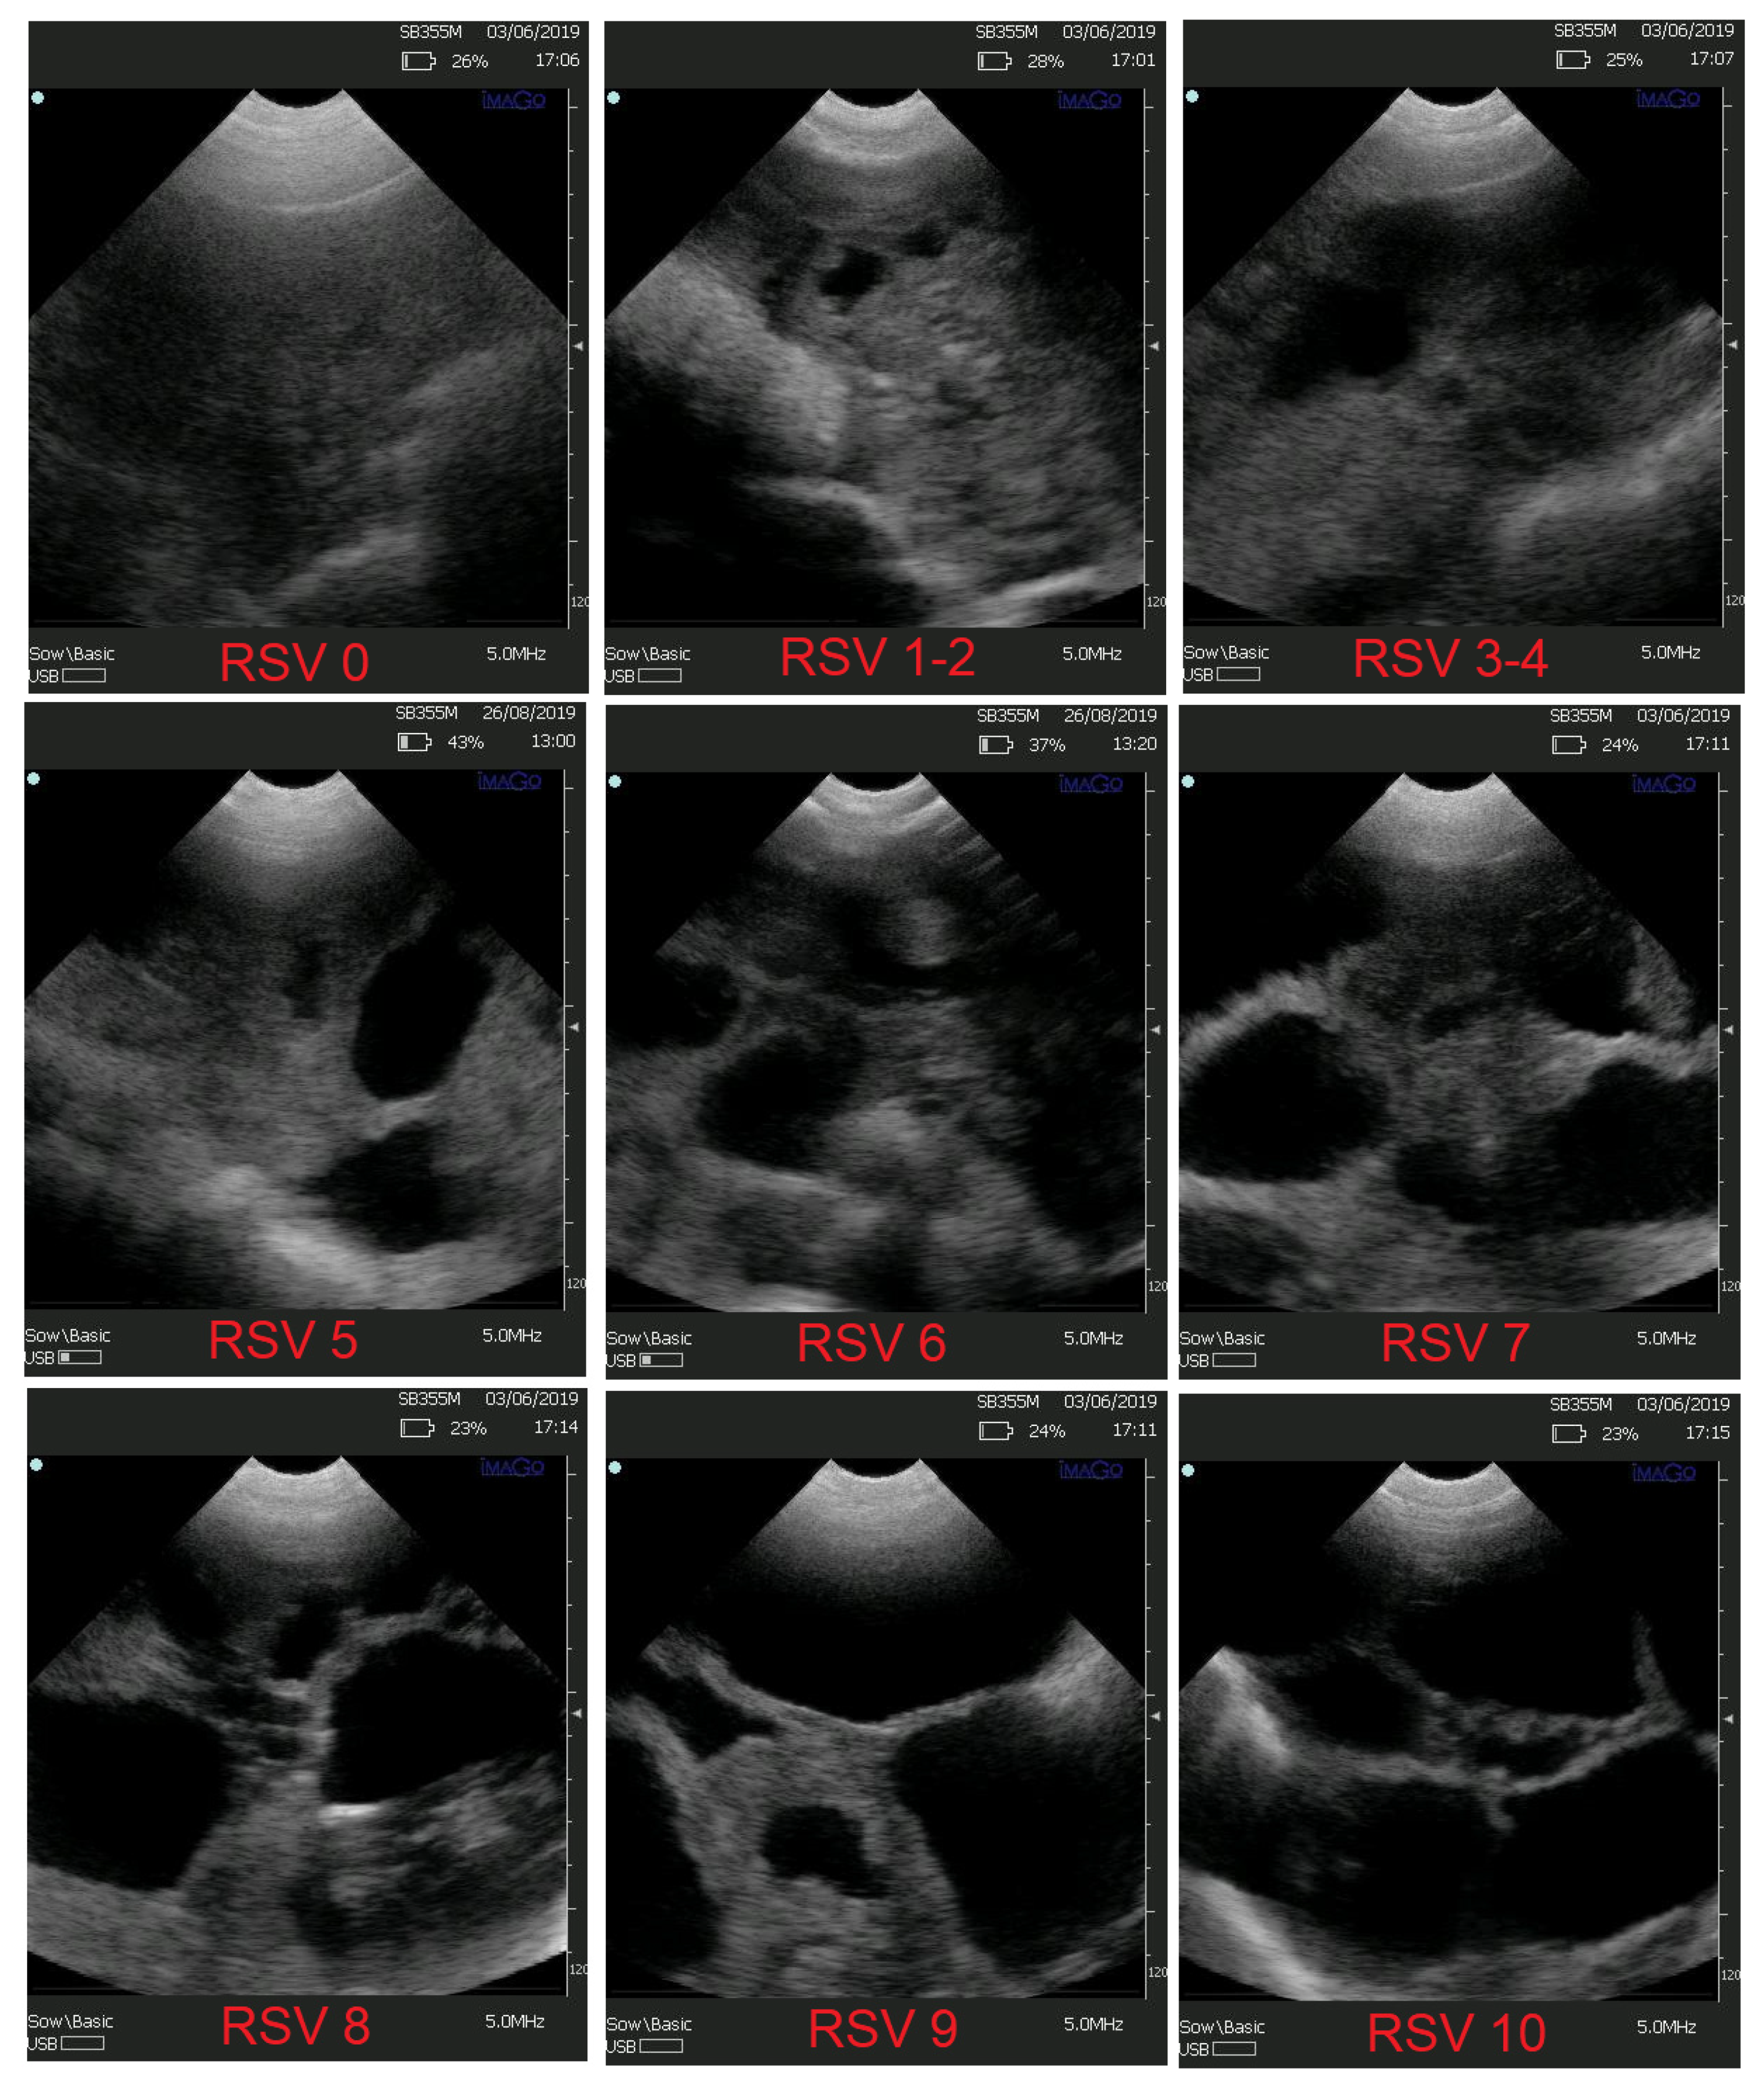

- 1st scan score (RSV1)

- 2nd scan score (RSV2)